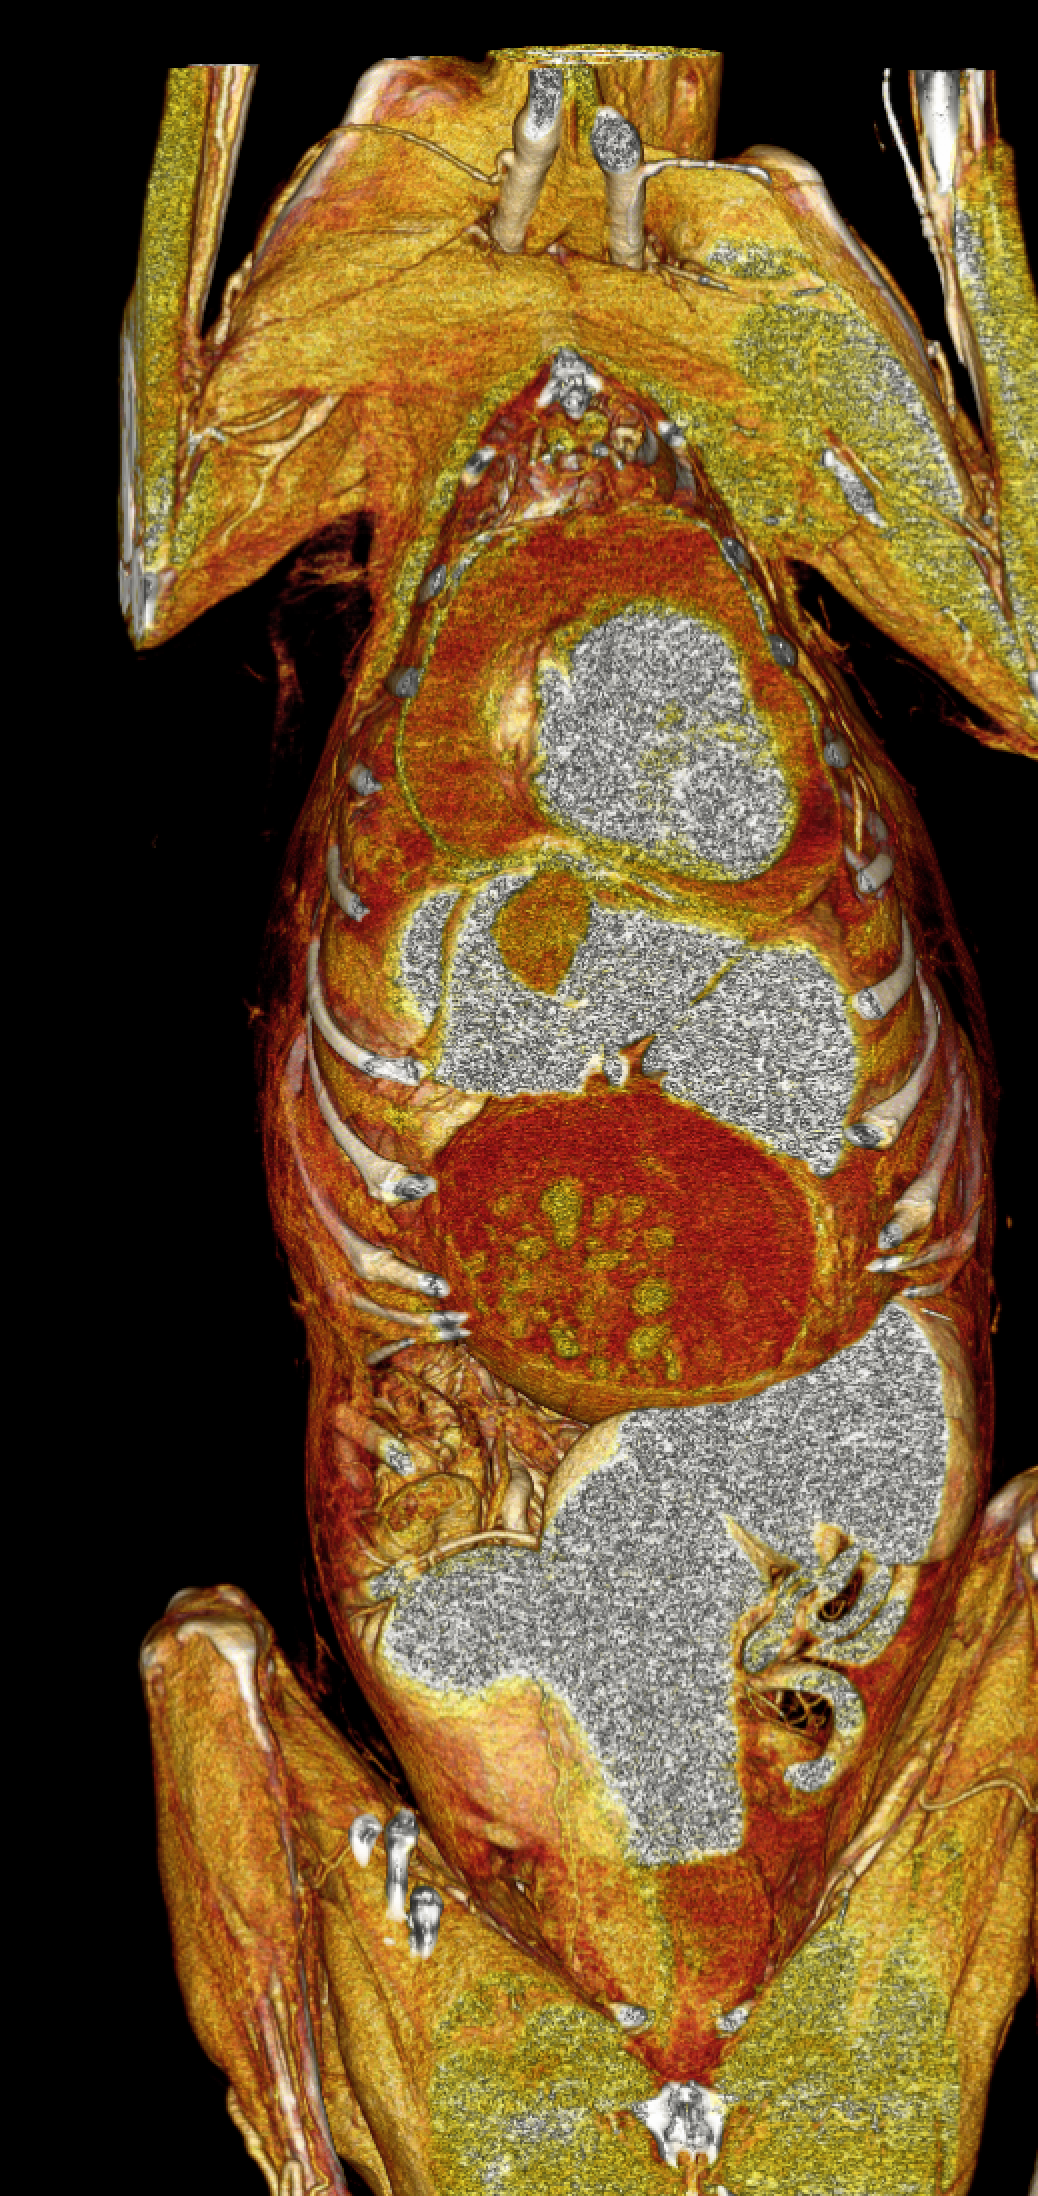

高齢(12歳)のアフガンハウンドが吐きたそうだけど、何も出てこない。次第に起立出来なくなったとのことで夜間に救急で来院しました。症状とエックス線検査から胃捻転と診断しました。また聴診時に心音は遠く、聴取出来ませんでした。胸部エックス線検査においてムーンハートが確認されました。超音波ガイドで出血性心のう水を2リットル抜去しました。バイタルサインが落ち着いたところで胃捻転整復術を実施しました。その後も出血性心のう水は貯留傾向にありました。高齢であることから血管肉腫が疑われましたが、各種画像診断においても腫瘤の存在はなくまた細胞診においても血管肉腫の可能性は低いものと判断しました。胃捻転から2週間後、心膜の生検と再発性の心膜貯留を回避する目的で心膜切除術を実施しました。心膜は顕著に肥厚し、線維化を伴っていました。病理検査の結果をもとに内科療法を併用する予定です。高齢ながら頑張ってくれました。